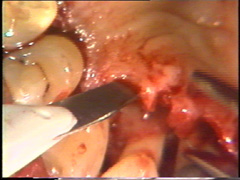

En las regiones dónde la morfología ósea impide un cierre adecuado del colgajo, se realizan recortes menores de la configuración del hueso. En este caso particular el  hueso de la superficie bucal del segundo premolar impide una adaptación del colgajo. El hueso es remodelado con un cincel, con golpes cortos y suaves. Este instrumento es preferible al uso del instrumental rotatorio, porque son más difíciles de controlar y la visión del profesional se entorpece por el uso necesario del refrigerante acuoso.